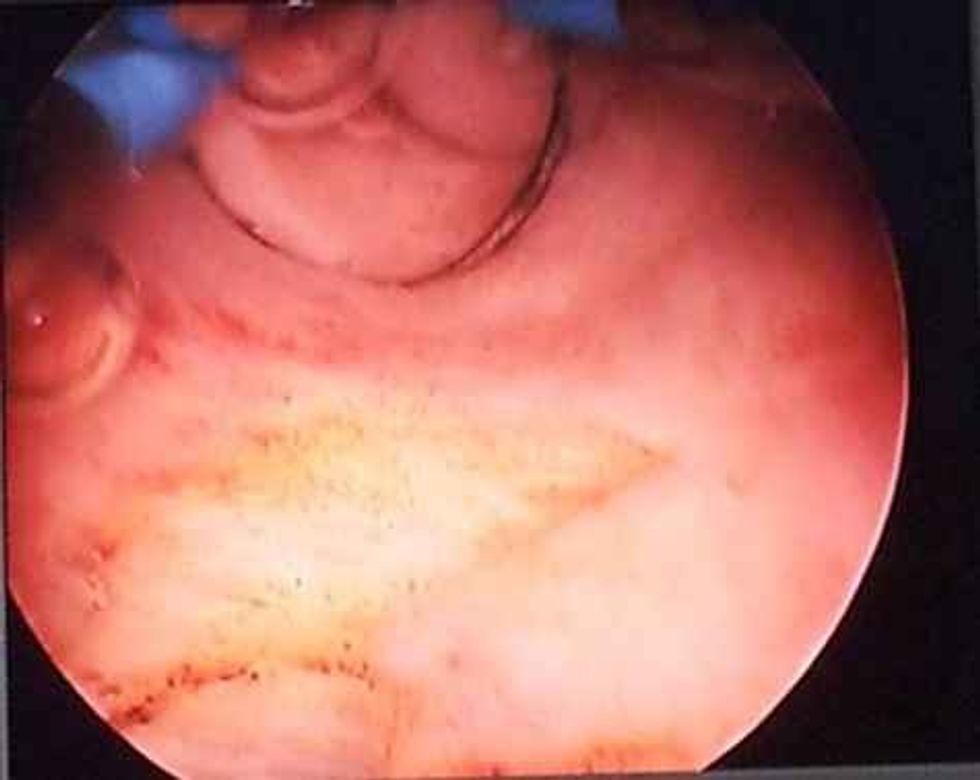

Më poshtë keni pamje nga operimi i septumit të mitrës në Klinikën Gjinekologjike Gjermane në Prishtinë: